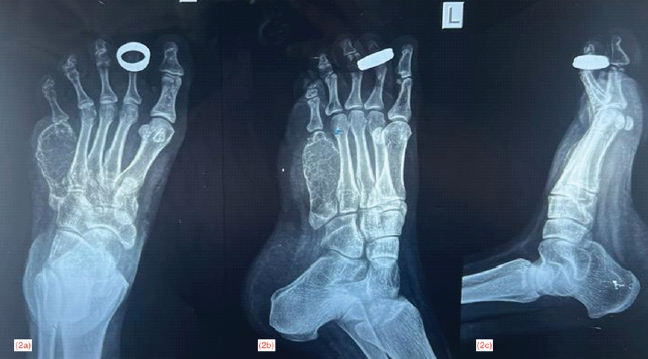

Radiograph of the left foot showed the presence of a meta-diaphyseal, expansile, osteolytic lesion, involving the entire shaft of the 5th metatarsal with minimal periosteal reaction. The lesion had the characteristic soap-bubble appearance with multiple internal septations. The tumor had a clear margin and the proximal and distal epiphyseal regions were not involved. The features were suggestive of a locally aggressive benign bone tumor (Fig. 2).

Figure 2: Radiograph of left foot anteroposterior (a), oblique (b), and lateral view (c) of left foot